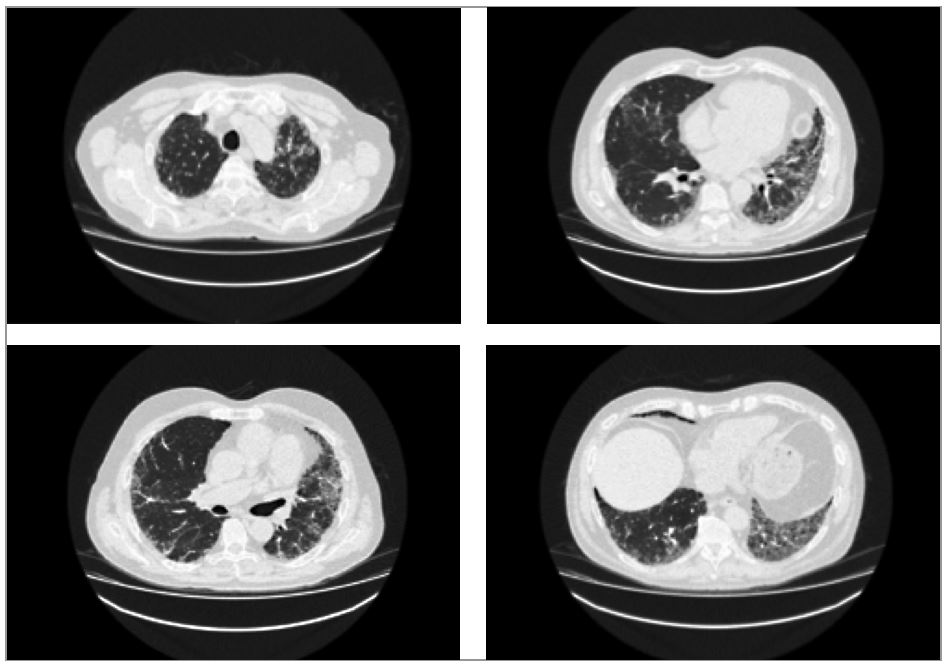

Рис. 3. ВРКТ-картина вероятной обычной интерстициальной пневмонии: выраженные ретикулярные изменения в кортикальных отделах с нарастанием их к диафрагме, обусловленные утолщением внутридольковых перегородок, тракционные бронхоэктазы, «сотовое» легкое, отсутствие «матового стекла».

- ВРКТ: КТ-картина вероятной обычной интерстициальной пневмонии (рис. 3).